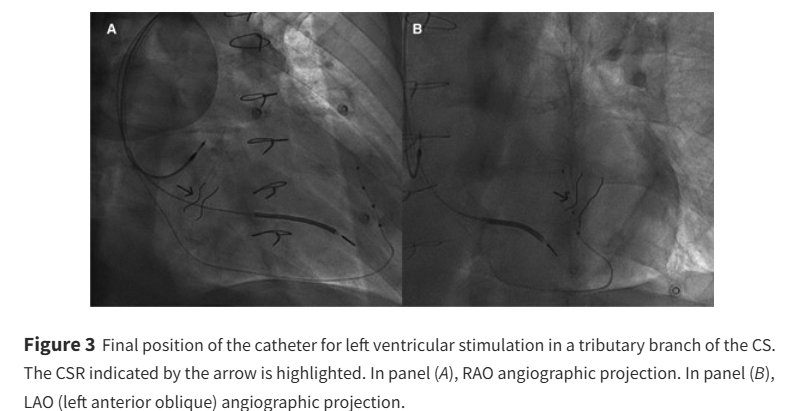

Is there room for CRT in patients with coronary sinus reducer devices? ow.ly/ZazN50VSn7N #EHJCaseReports Philipp Sommer Tee Joo YEO Aaysha Cader Boldizsar Kovacs Erik Rafflenbeul A.Nazmi Calik Obayda Azizy Sara Moscatelli EHJCaseReports Editor-in-Chief #CardioX #EPeeps